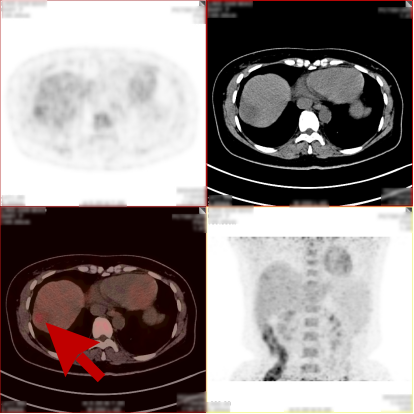

病史:女,48岁,无明显不适,健康查体,无特殊病史及手术史。乙肝大三阳,AFP:380.21ng/mL,CA199:33.24U/ml,CA125、CA153、CA724、 CEA(-)。

PET/CT检查所见

1、肝 S8 段见 1 个稍低密度软组织肿块,病灶内部分组织代谢增高,考虑肝细胞肝癌;

2、肝 S8 段另见 1 个稍低密度结节,代谢轻度增高,考虑为小肝癌或肝内子灶形成,该压迫相邻肝中静脉。

PET/CT活检病理:原发性肝癌